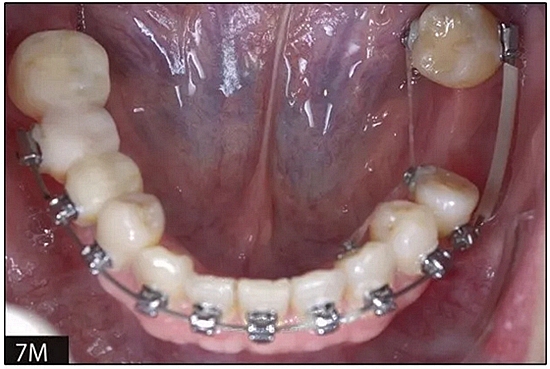

完全固定的Damon Q設(shè)備(加利福尼亞州Glendora的Ormco)與制造商指定的弓絲和附件一起使用。下頜弓,一開(kāi)始放入0.014英寸的鎳鈦弓絲,5個(gè)月后放入0.014×0.025英寸的鎳鈦弓絲。舌側(cè)扣和鏈圈放置在下頜尖牙和第二前磨牙上以控制扭轉(zhuǎn)。在治療的第7個(gè)月,將下頜弓絲換成0.017× 0.025英寸的β鈦絲。另一個(gè)舌側(cè)扣和鏈圈放置在下頜左側(cè)第三磨牙上以提供近中牽引力(圖9)。在16個(gè)月的治療結(jié)束時(shí),所有的扭轉(zhuǎn)都得到了矯正,缺牙間隙縮小到8 mm(圖8),但由于頰側(cè)骨板的嚴(yán)重吸收,牙槽嵴的寬度仍然很窄(約3 mm)(圖9)。通過(guò)正畸移動(dòng)下頜左側(cè)第二前磨牙,在前磨牙之間產(chǎn)生一個(gè)種植部位。在第一和第二前磨牙之間的弓絲上放置一個(gè)推簧,并將舌側(cè)扣和鏈圈放置在第一前磨牙和第三磨牙之間(圖9),在頰側(cè)和舌側(cè)施加力。施力均為輕力,每個(gè)表面上約2盎司(28.3 cN)以控制牙根側(cè)面的吸收。

圖8